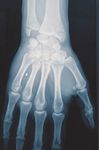

C1 Fraktur, Versorgung mit volarer Platte (breit)

Präoperativ

Postoperativ

Klinischer Fall und CT-Aufnahmen mit freundlicher Unterstützung der

Klinik und Poliklinik für Unfall-, Hand- und Wiederherstellungschirurgie

Universitätsklinikum Gießen und Marburg GmbH